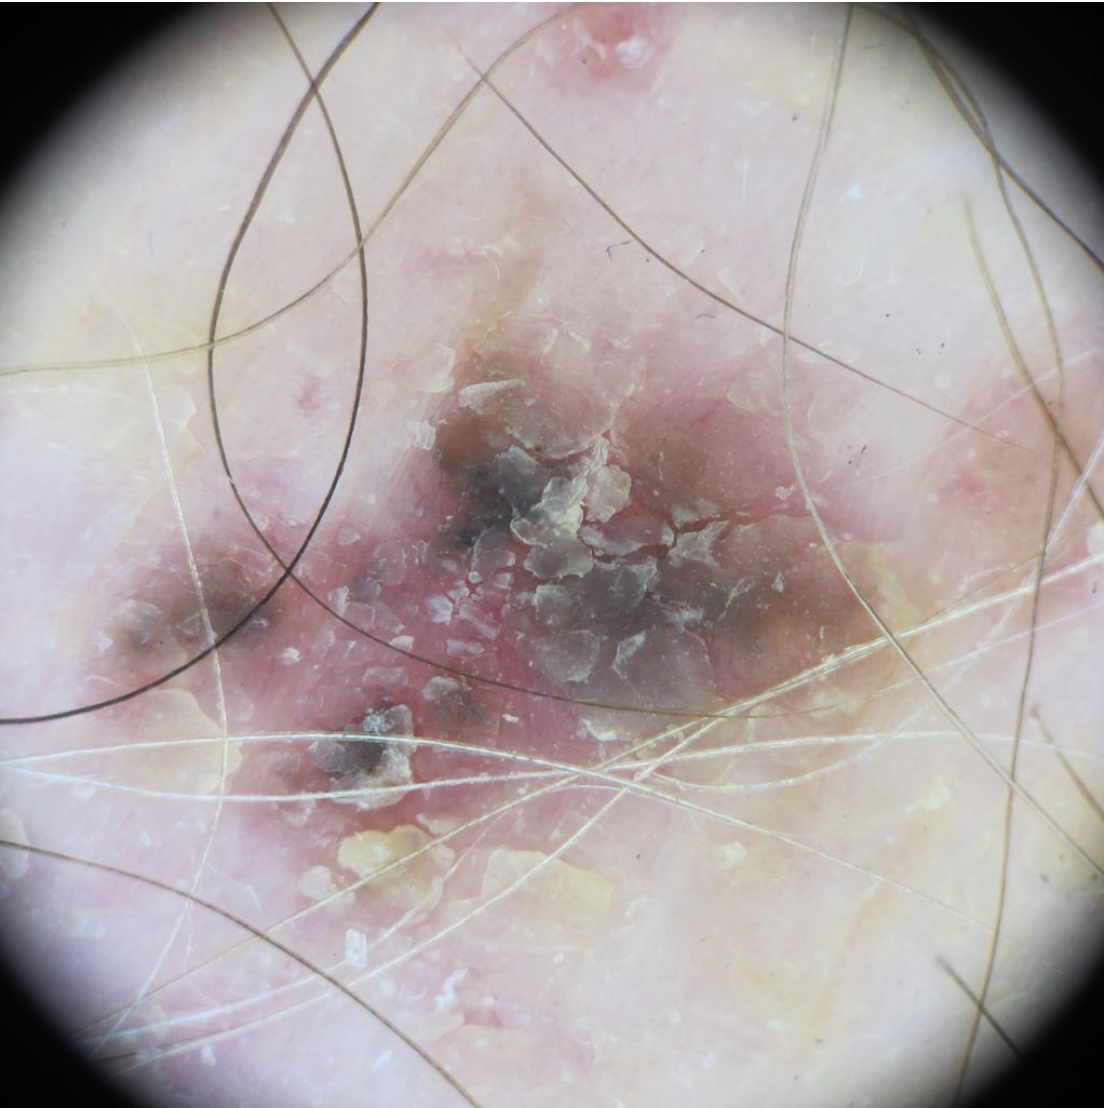

Actinic Keratosis (AK) Photos

Actinic keratosis on head or neck. Photo: International Skin Imaging Collaboration at isic-archive.com

Actinic keratosis on posterior torso. Photo: International Skin Imaging Collaboration at isic-archive.com